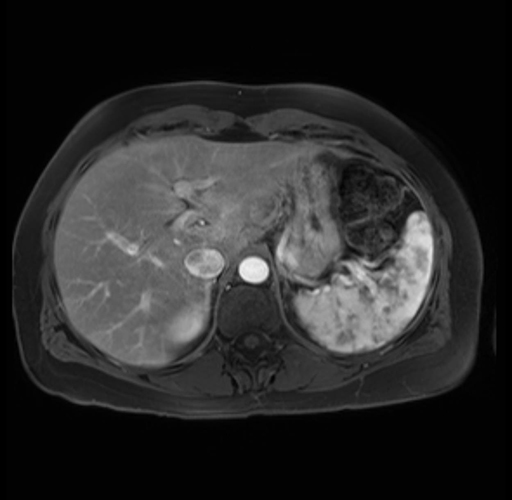

Imaging Analysis

Look through the patient's CT scan to identify any areas of concern for the necessary procedure.

Based on your CT findings, which issue(s) are present and would give reason for "planned slowing down moment(s)" in this case?